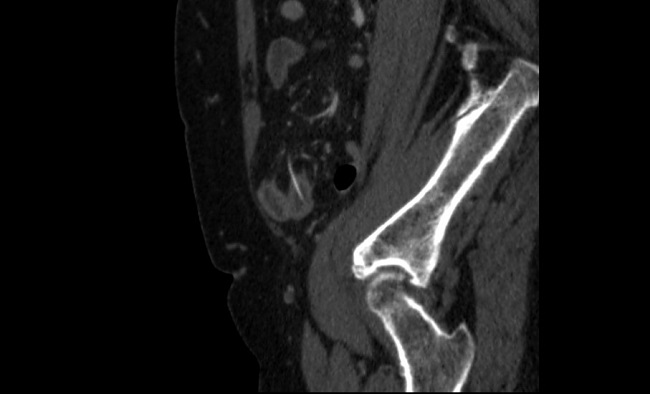

Ante la firme sospecha de abdomen agudo quirúrgico, previa valoración del equipo quirúrgico de guardia, se solicitó directamente una tomografía computarizada que mostró una perforación contenida de íleon distal secundaria a CE radio-opaco, como se aprecia en las imágenes 1 y 2.

Imagen 1. TC en proyección sagital. Se observa una imagen radio-opaca lineal que perfora de manera transmural un asa de intestino delgado.